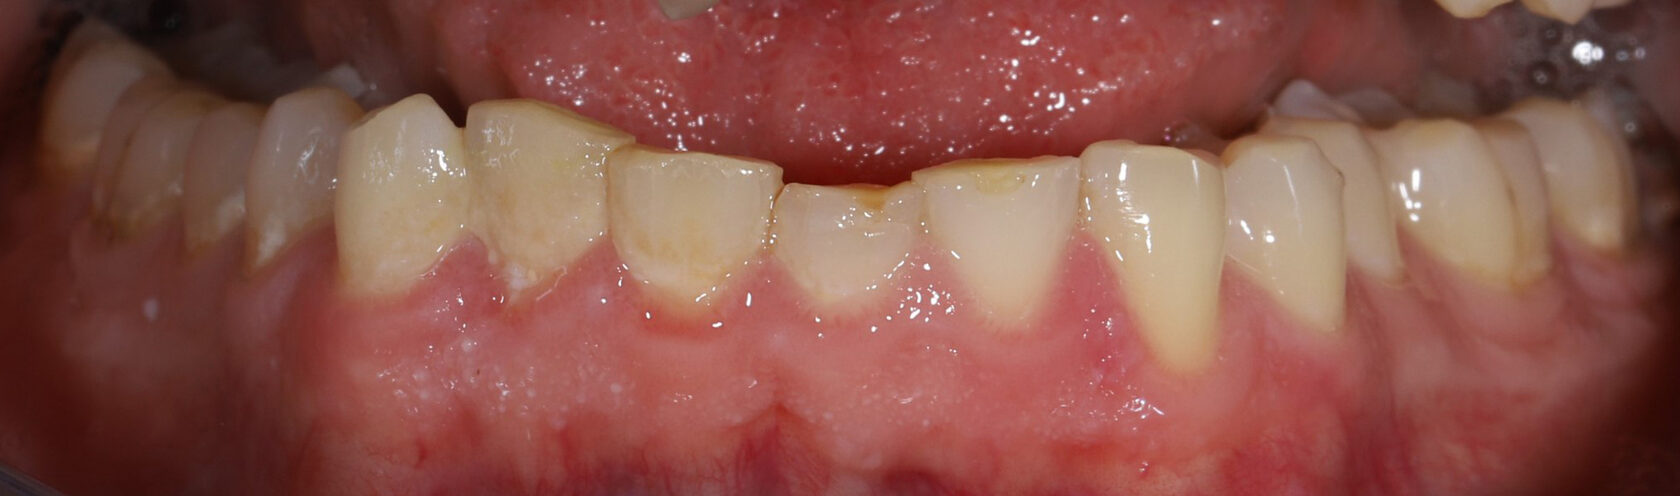

Эстетическая реабилитация винирами при генерализованной стираемости зубов